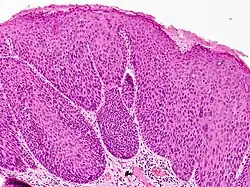

Bowenoid papulosis diagnosis requires a history, histologic examination, and clinical description of the condition.[9]